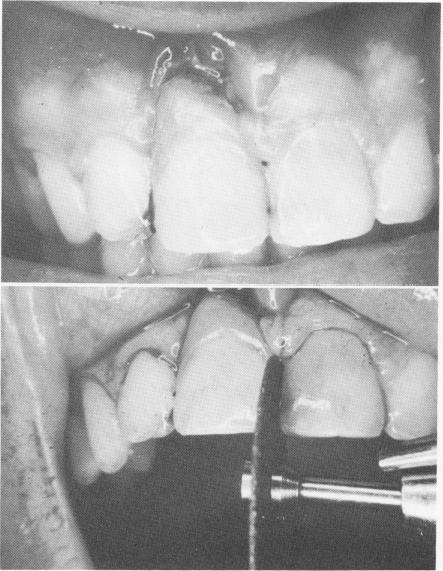

Fig. 8-39. A, Inflammation and hypertrophy are seen above the acrylic crown. B, With a carborundum disk, the wires of the A-splint are disked away on the mesial and distal aspect of the restoration, freeing it from its support.

1 Inflammation, hypertrophy above endosseous pin implant acrylic crown

2 Disc away A-splint wire at proximal side of pin implant restoration